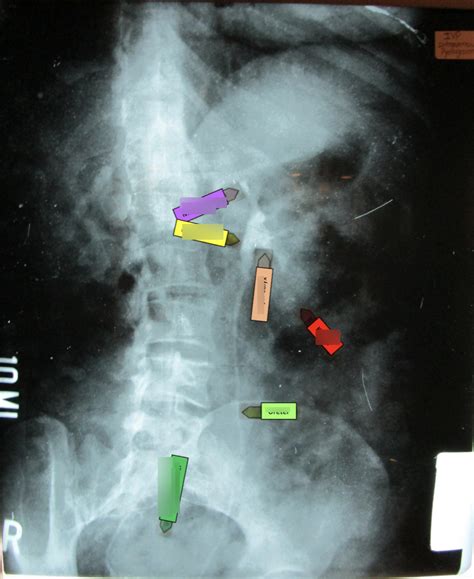

Ureters: The Urine Highways

The ureters are the tubes that transport urine from the kidneys to the bladder. On an IVP, we can see the ureters’ course as they descend from the kidneys. We can assess their width and look for any blockages, such as kidney stones, or compressions. The IVP allows us to observe peristaltic movement, the wavelike contractions that propel urine down the ureters. This is super important because any obstruction in the ureters can lead to a buildup of urine, potentially causing pain and kidney damage. This visualization is essential for making a diagnosis.